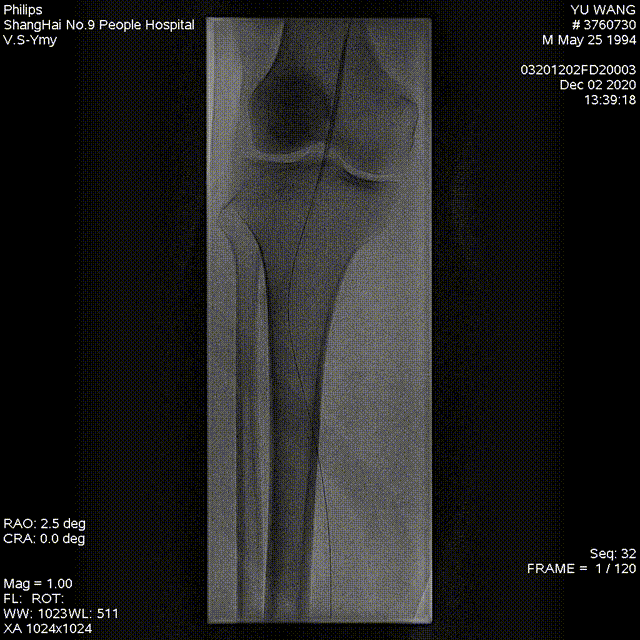

★ 病例基本情况

84岁女性患者,因"右足背、拇趾溃疡半年,支架植入术后4年余"就诊。患者4年前因下肢缺血行支架植入术,近期症状复发加重。

图:术前CT

★ 术前评估

血管造影显示股腘动脉长段支架内再狭窄,伴有严重钙化。

★ 术中造影

图:术中造影